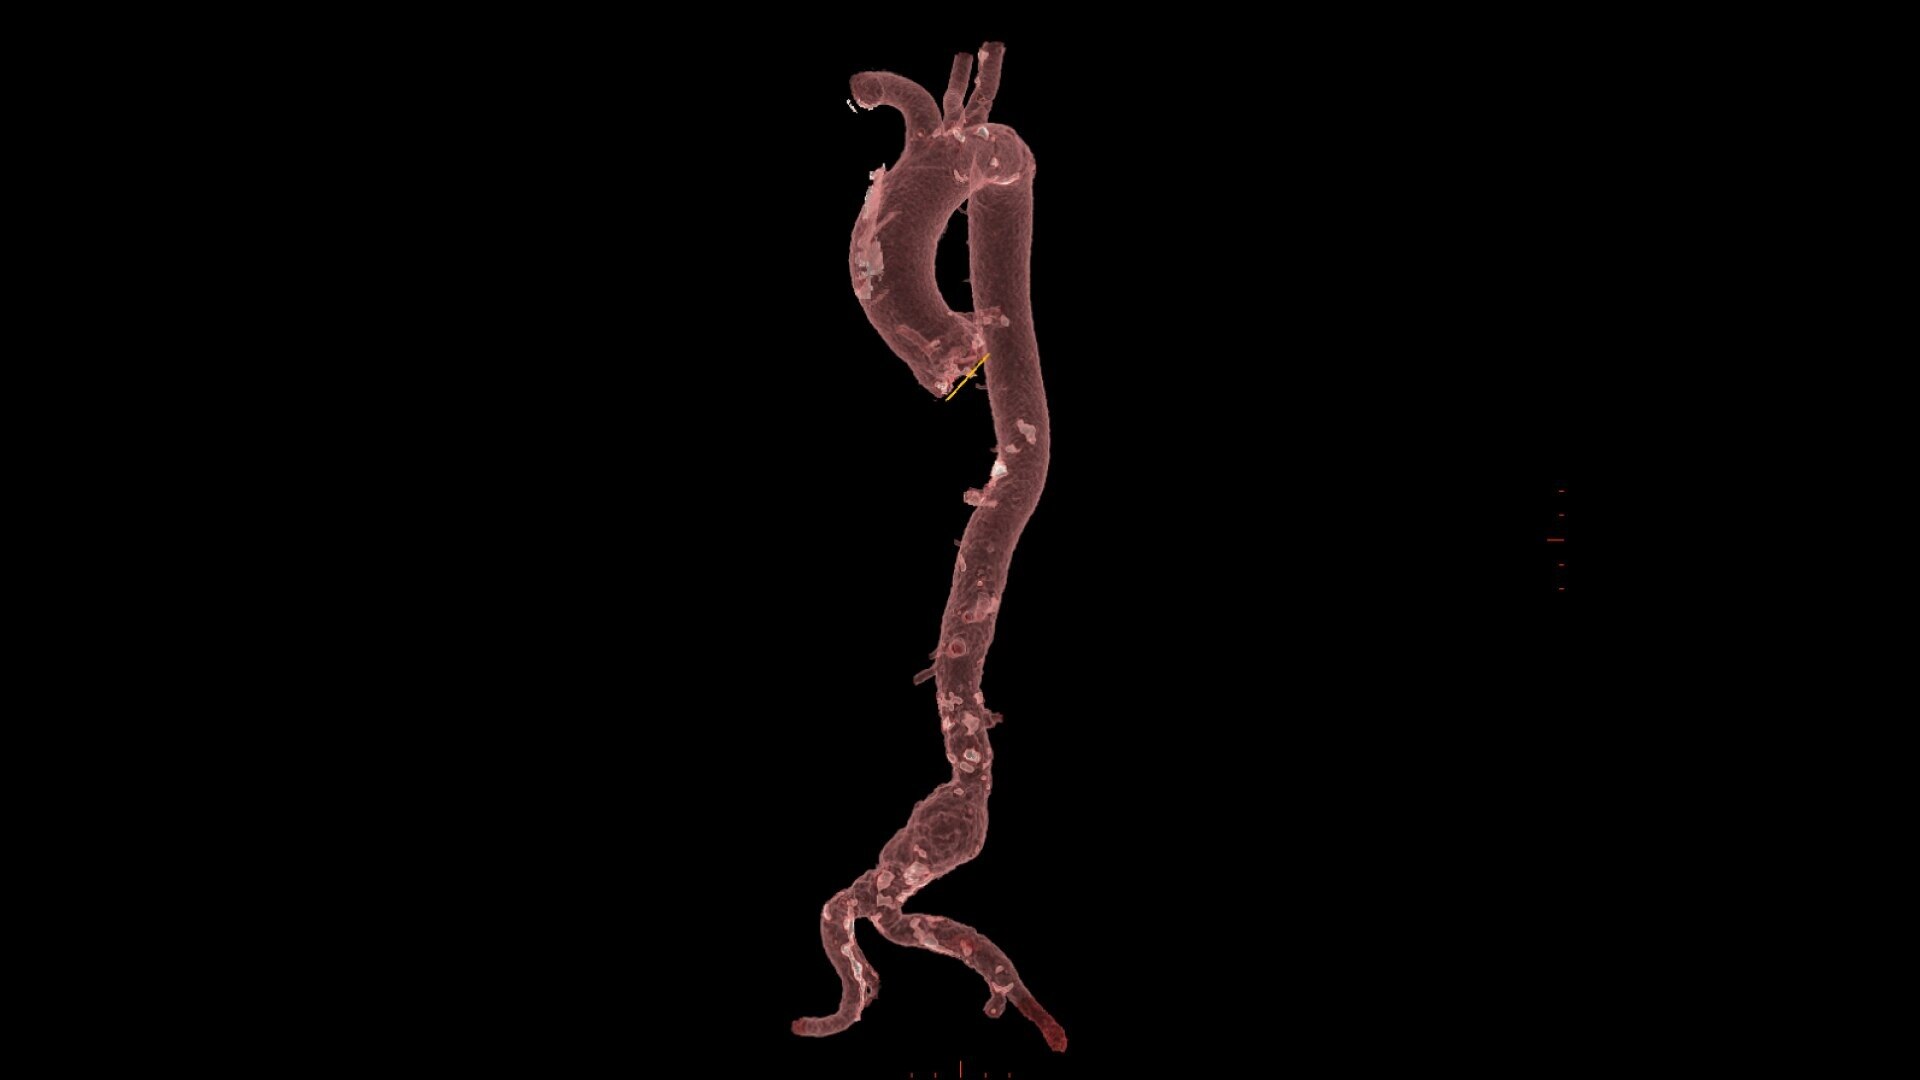

PLAN

0-click aorta segmentation and valve definition makes accurate valve sizing accessible to anyone.

GUIDE

3D fusion guidance enhanced with Calcification Enhancement improves the visualization of moving contrasted structures.